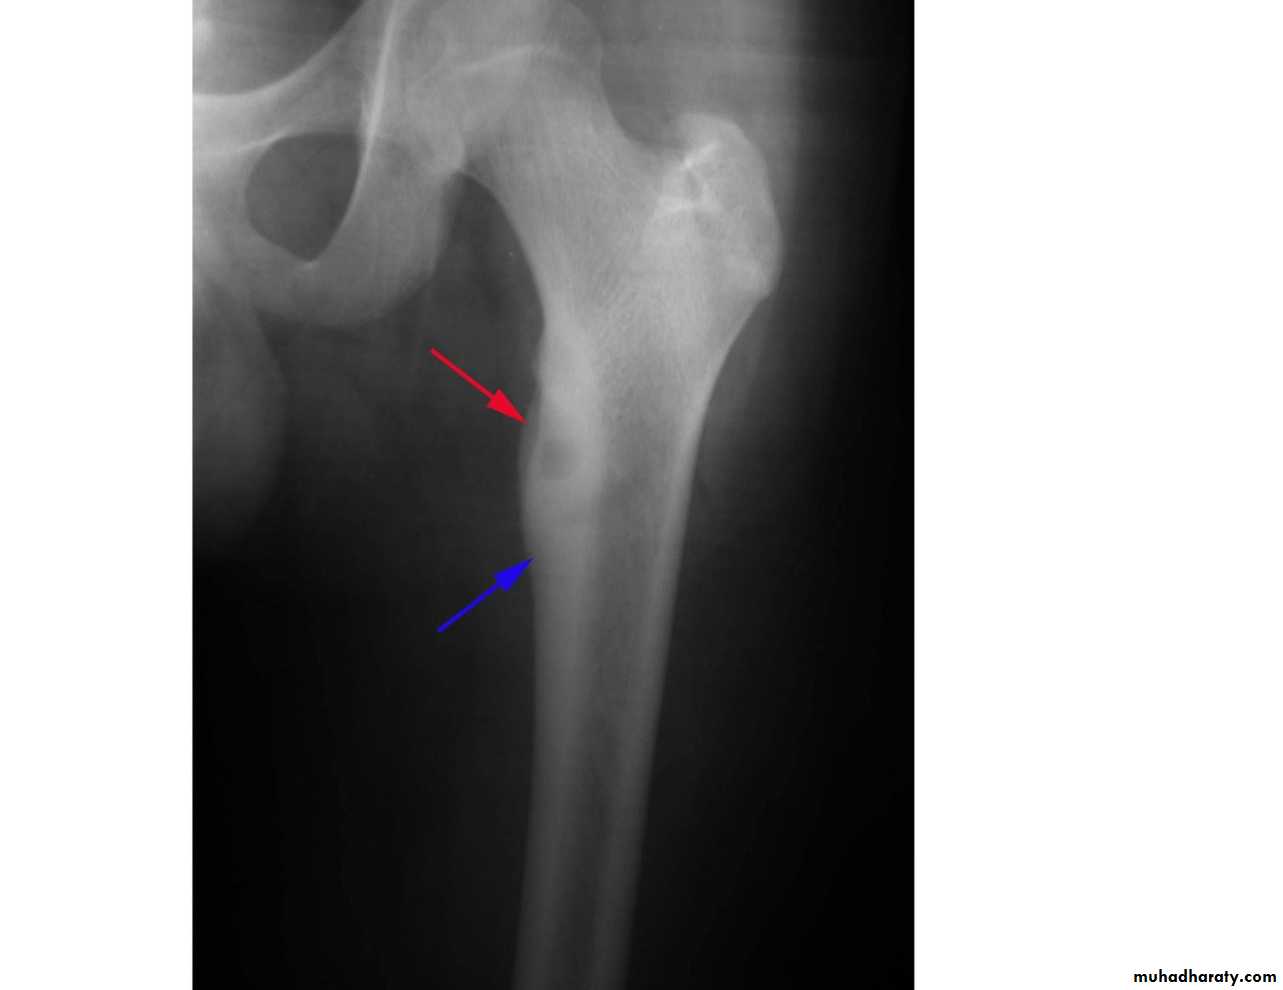

shepherd crook deformity seen in fibrous dysplasia

A shepherd crook deformity refers to a coxa varus angulation of the proximal femur, classically seen in femoral involvement by fibrous dysplasia .The whole vertebral body marked by vertical striation … being Haemangioma

A shepherd crook deformity refers to a coxa varus angulation of the proximal femur, classically seen in femoral involvement by fibrous dysplasia